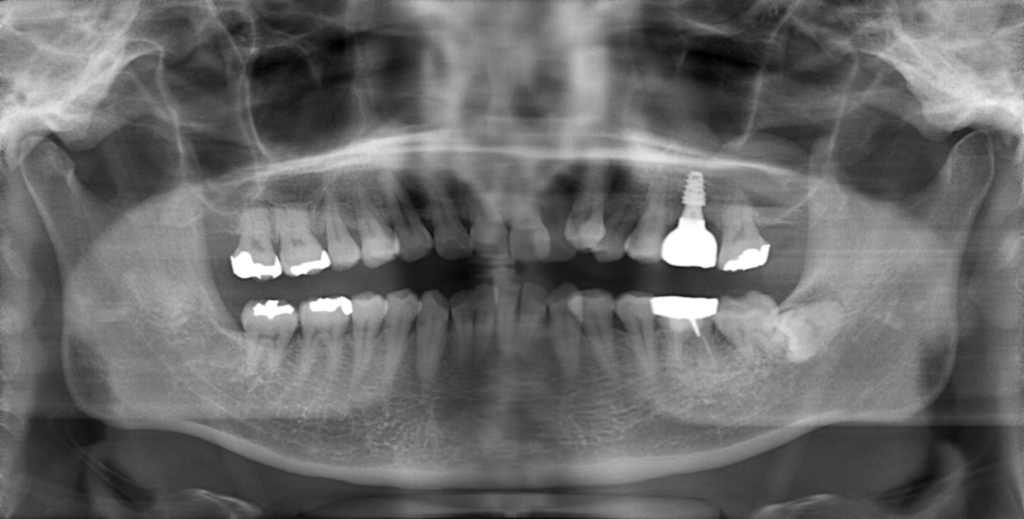

Y様インプラント実例 #44

左の上下の奥歯をインプラントで治療しています。

左下の奥歯は歯を抜くのと同時にインプラントの埋め込みを行っています。

被せものは上下、セラミックスで作っています。

治療前

治療後